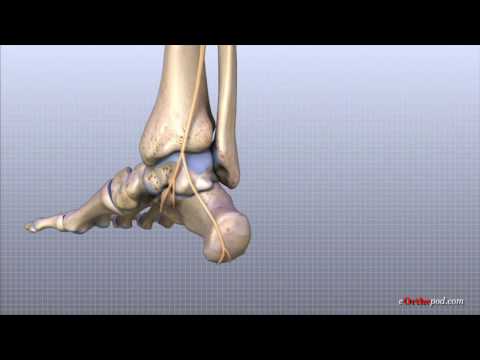

Bàn chân và cổ chân tạo nên một cấu trúc giải phẫu phức tạp bao gồm 26 xương hình dạng không đều, 30 khớp hoạt dịch, hơn 100 dây chằng và 30 cơ tác động lên các phân đoạn. Tất cả các khớp phải tương t

Oct 21, 2022Các xương cổ chân. Gồm 7 xương sắp xếp thành hai hàng: Hàng sau: tất cả hai xương là xương sên với xương gót. Hàng trước: tất cả 5 xương là xương ghe, xương vỏ hộp và ba xương chêm. Xương